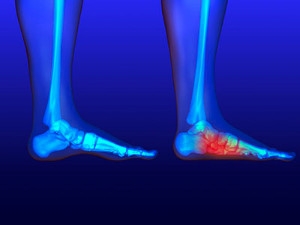

Treatments for a Broken Ankle

Ankle fractures occur when one or more of the bones that make up your ankle breaks. This can cause symptoms such as pain, bruising, tenderness, swelling, weakness, numbness, and difficulty putting weight on your ankle or walking. Ankle fractures may be treated with support devices, such as a brace or cast, that immobilize and protect the affected ankle to encourage healing. If you have a cast or brace, you may need to walk with crutches for a period of time. The pain of an ankle fracture can be relieved through over-the-counter medications that your podiatrist recommends. A broken ankle may need to be treated surgically if the fracture is severe. If you have broken your ankle, it is suggested that you seek the care of a podiatrist.

Broken Ankles

A broken ankle is experienced when a person fractures their tibia or fibula in the lower leg and ankle area. Both of these bones are attached at the bottom of the leg and combine to form what we know to be our ankle.

When a physician is referring to a break of the ankle, he or she is usually referring to a break in the area where the tibia and fibula are joined to create our ankle joint. Ankles are more prone to fractures because the ankle is an area that suffers a lot of pressure and stress. There are some obvious signs when a person experiences a fractured ankle, and the following symptoms may be present.

All About Broken Ankles

Broken ankles are a serious injury that can lead to an inability to walk, function, and also cause a significant amount of pain. A broken ankle is a break in one of the three bones in your body that connect at the ankle joint: the tibia, the fibula, and the talus. The tibia and fibula are your two primary leg bones that connect at the knee, which sit directly upon the talus bone. This is protected by a fibrous membrane that allows for movement in the ankle joint. A broken ankle is usually caused by the foot rolling under or twisting too far, causing one of these three bones to snap.

A broken ankle is different from an ankle sprain, which occurs when the ankle ligaments are ripped or torn but no bones have been broken. A sprain can still be very severe, causing bruising in the foot and an inability to hold your own weight, much like a broken ankle would. If you’re unable to stand, and suspect that you have a broken ankle, the first thing to do would be to get an immediate X-ray to determine the severity of the break.

A common cause of broken ankles is when the ankle is rolled over with enough pressure to break the bones. This usually happens during exercise, sports, or other physical activity. Another common cause is a fall or jump from a tall height.

One immediate treatment for pain relief is elevating the foot above your head to reduce blood flow to the injured area. You can also apply ice packs to your ankle to help reduce swelling, redness, inflammation, and pain. After these initial steps, getting a cast and staying off your feet as much as possible will aid in the recovery of the broken ankle. The less movement and stress the ankle has to endure, the more complete it will heal. A doctor can determine if surgery is needed in order to heal correctly. In these cases, an operation may be the only option to ensure the ability to walk properly again, followed by physical therapy and rehabilitation.

It is highly important to determine if surgery is needed early on, because a broken ankle can become much more severe than you realize. If not professionally treated, the broken ankle will inhibit your walking, daily functioning, and produce a large amount of pain. Treating your broken ankle early on will help prevent further damage to it.